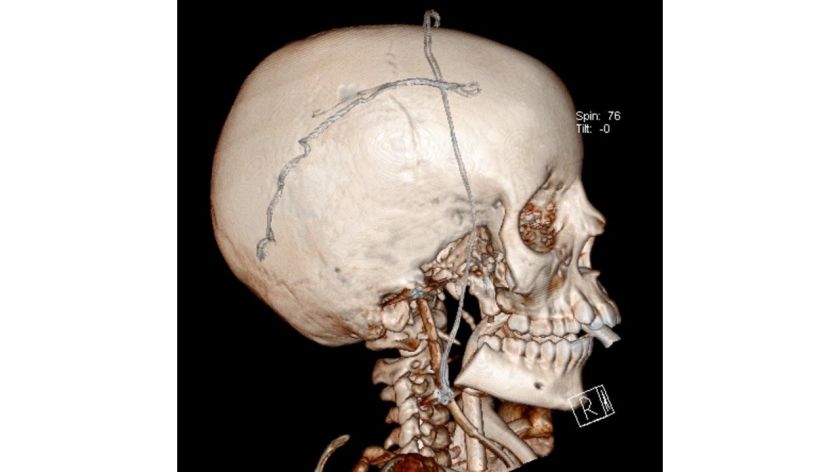

Kartu su naviku reikėjo pašalinti žandikaulio sąnarį, skruostikaulį ir kaukolės pamato dalį, paausinę seilių liauką, dalį sveikų audinių – tokia yra radikalaus gydymo taktika: „Galvoje ypatingai daug svarbių anatominių struktūrų – arterijų ir venų, tarp kurių ir miego arterija, nervų, kuriuos reikėjo išsaugoti, nepažeisti, išvengti ypač gausaus kraujavimo komplikacijų, – operacijos subtilybes aiškina gydytoja chirurgė O. Kutanovaitė. – Kadangi pacientas vaikas, reikėjo prieš operaciją numatyti būsimas rekonstrukcines operacijas – kaip atkurti / suprotezuoti pašalintas kaukolės ir žandikaulio dalis, kai baigsis vaiko augimo procesas.“

Neurochirurgijos centro vadovas prof. Saulius Ročka sako, kad tokios operacijos – kompleksinė chirurgija – suteikia galimybę skirtingų sričių chirurgams dirbti kartu ir atlikti sudėtingą operaciją visiškai netipinėje vietoje: „Neurochirurgai turi patirties operuojant kaukolės pamatą, tačiau šiuo atveju navikas apėmė keletą sričių. Dar daugiau – šiuo atveju pacientas yra augantis vaikas, todėl operacija įmanoma tik bendradarbiaujant su onkologais ir veido žandikaulių chirurgais. Operacijos metu, išsaugant svarbias nervo dalis ir nepažeidžiant kraujagyslių, kartu su dalimi žandikaulio pašalinta kaukolės pamato dalis ir dangalas, kuris pakeistas kitu jungiamuoju audiniu – smilkininio raumens fascija.“